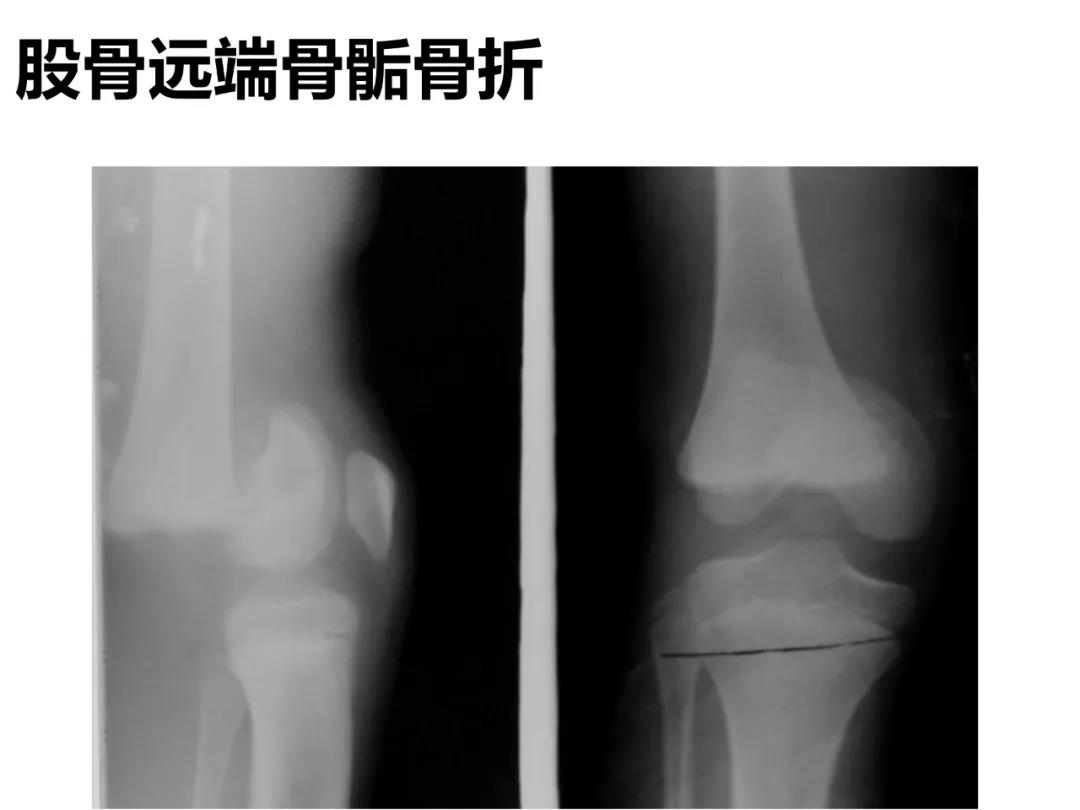

小儿骨科X线片汇总,临床读片宝典!